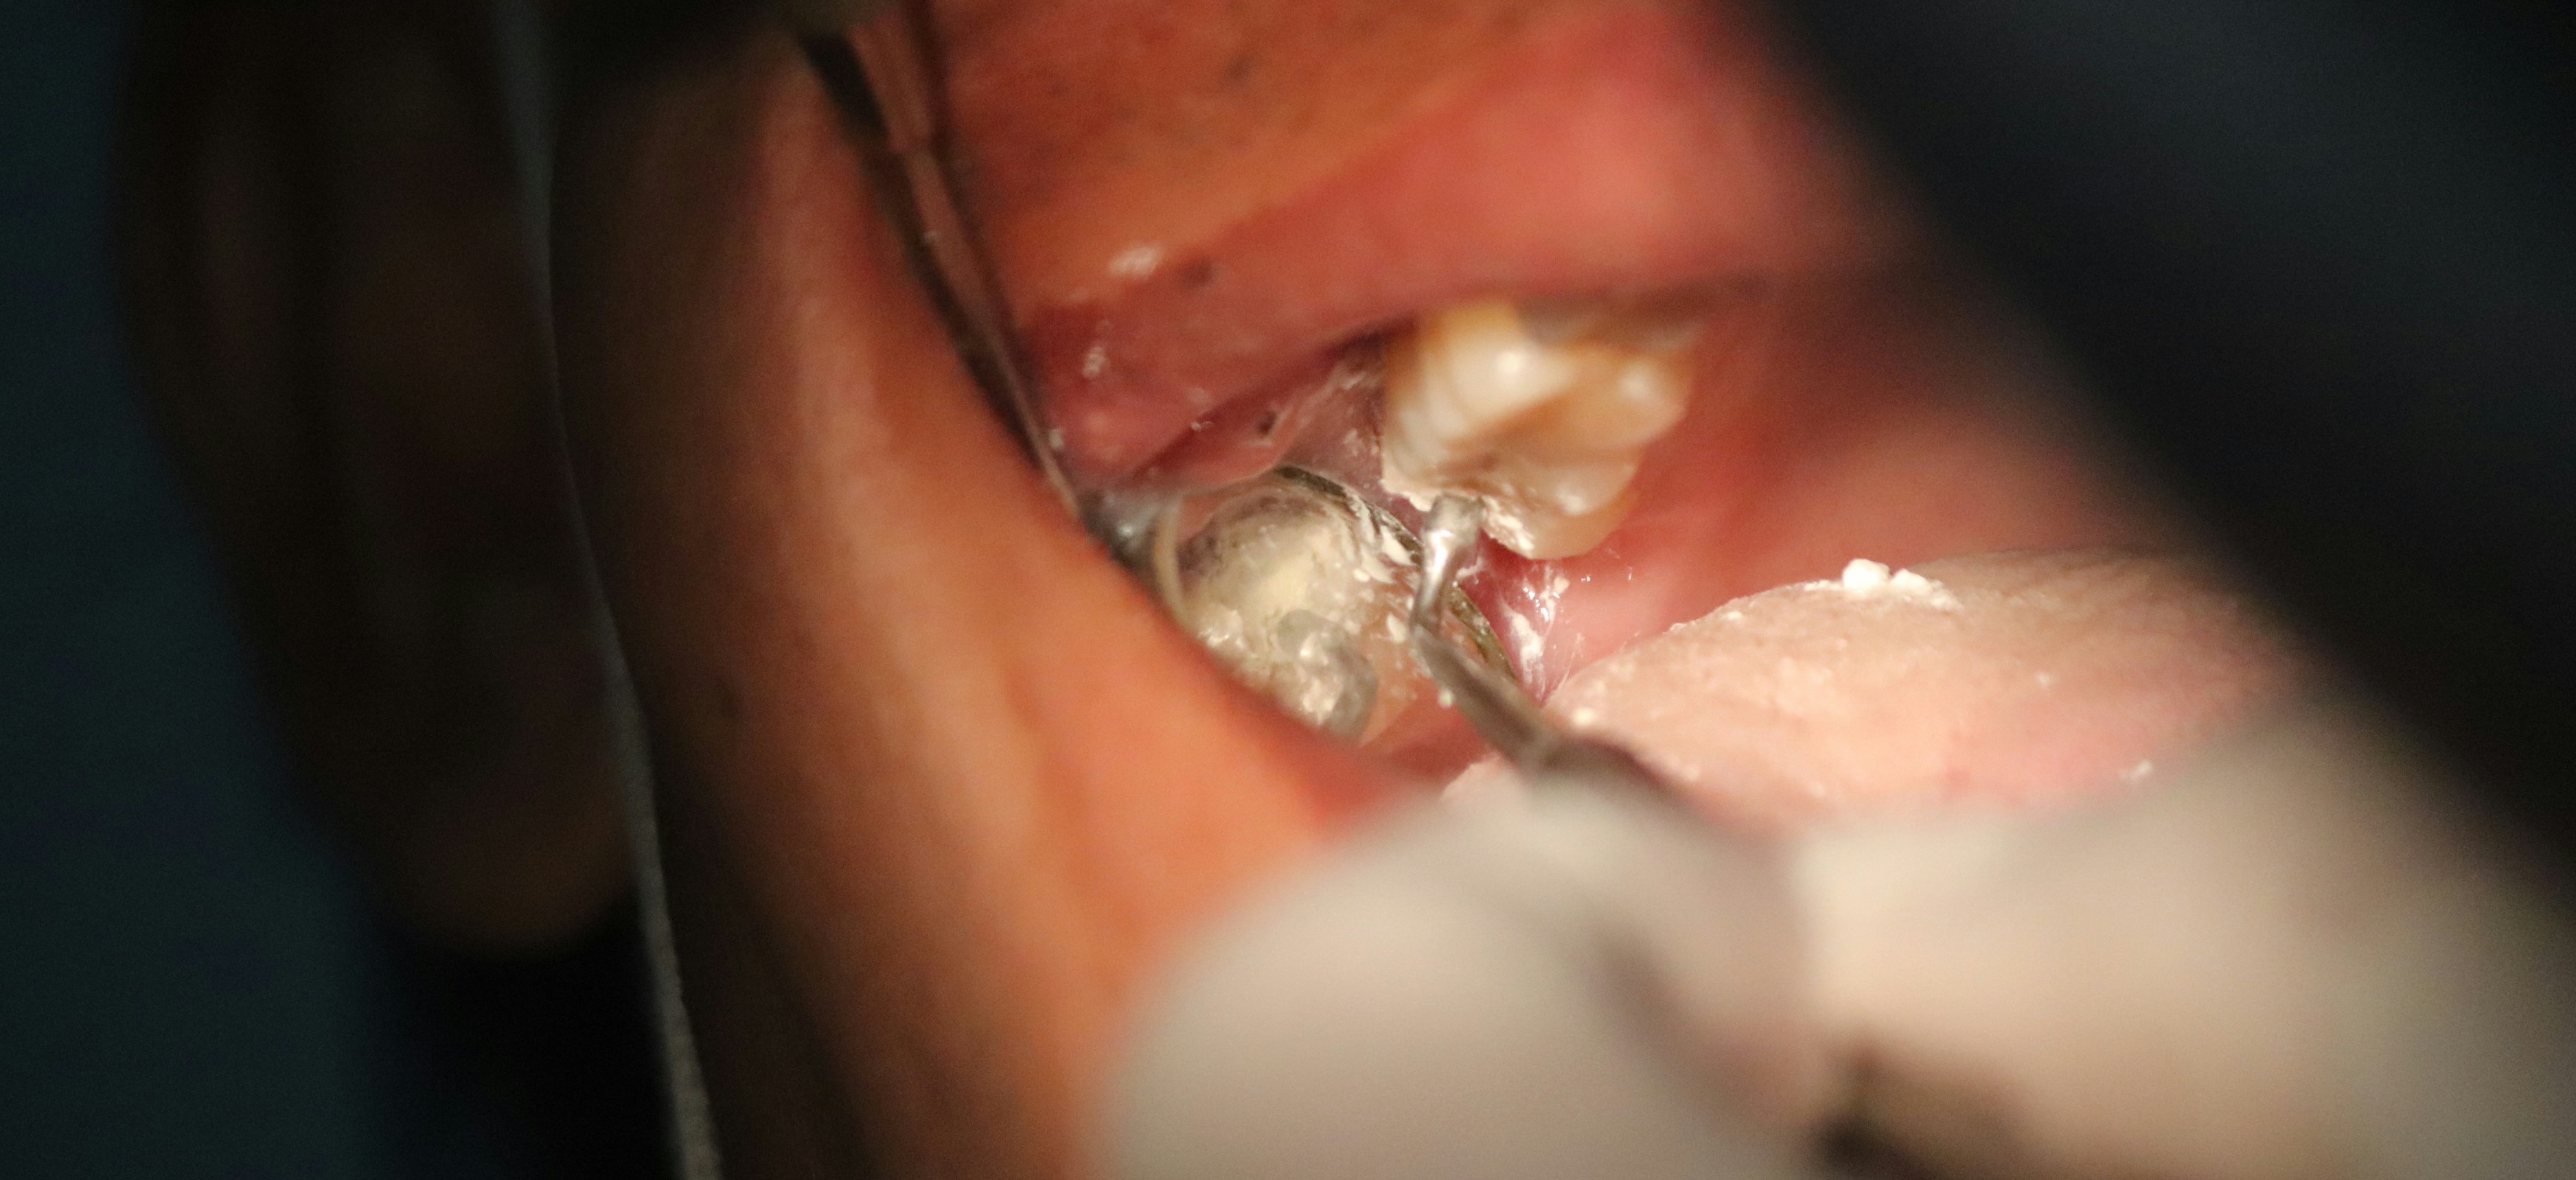

Spottsten, även kallat sialolit eller spottkörtelsten, är små förkalkade avlagringar som bildas i spottkörtlarna, oftast i underkäkens spottkörtel (glandula submandibularis). Dessa stenar kan blockera flödet av saliv vilket kan orsaka smärta och svullnad, särskilt i samband med måltider.

2. Större stenar: Kräver ibland att läkare avlägsnar stenen genom ett mindre kirurgiskt ingrepp.